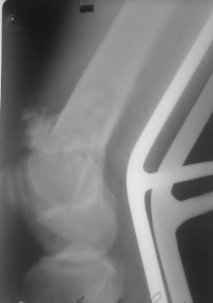

Уважаемые коллеги, прооперирована пациентка антеградным штифтом Остеомед, костная пластика не проводилась. Выбранный штифт по каналу бедренной кости на фоне отсутствия переднего кортикала в канале не центрируется. Технически неприятно, отсутствие передней и внутреннебоковой стенки до зоны мыщелков сильно затрудняло репозицию. Получилась вот такая картина. После стабилизации - очевидное повреждение ПКС и боковая нестабильность. В общем и далее будет чем заняться. Нам и в дальнейшем будет очень интересно мнение коллег.

НО> Получилась вот акая картина.

Молодцы, здорово получилось. Как ввдили самый дистальный винт? Надколенник не мешал?

Пробовали цетрировать штифт спицами, да не вышло... прет спереди и всё, картину тока портит))

А надколенник мешал слегка, но... штифт слегка предмоделирован до начала операции и угол введения дистального винта был градусов на 15 изменен, в итоге серьезной помехи надколенник не создал.